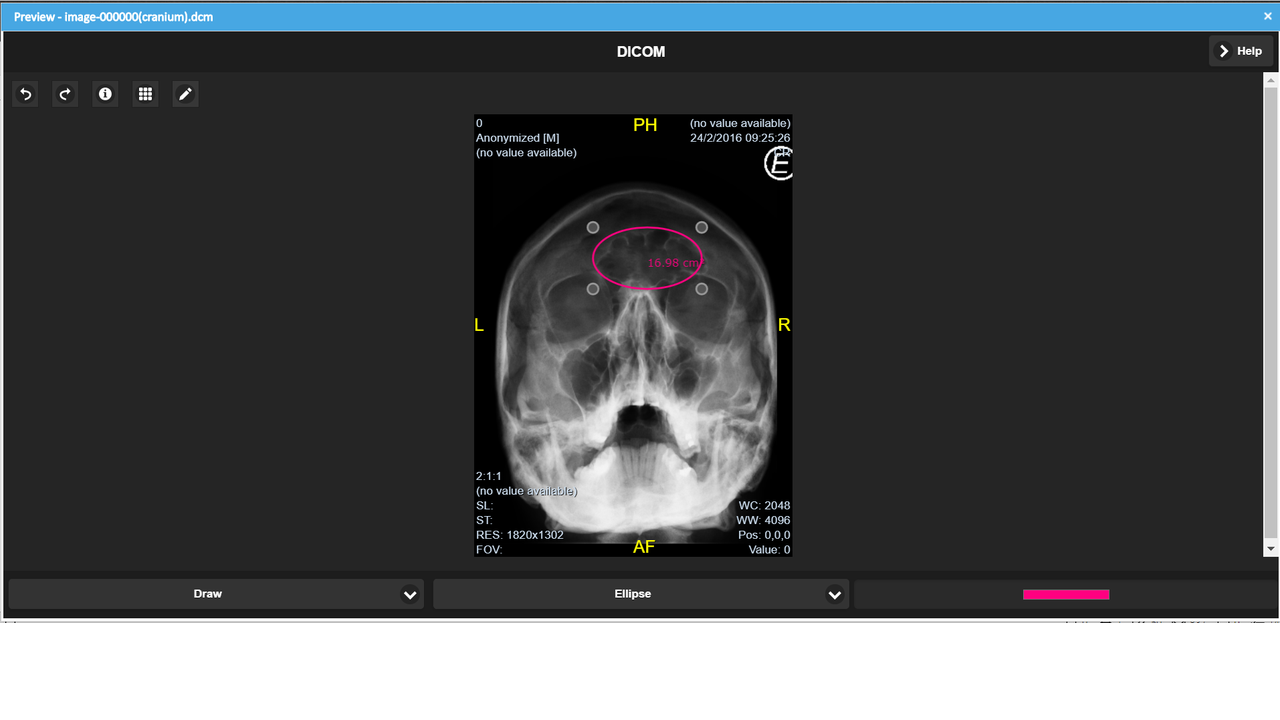

Ab LogicalDOC 8.3 ist die Vorschau von medizinischen Dokumenten im DICOM-Format verfügbar.

Einzelheiten der Funktion

- Werkzeuge zum Messen von Abständen, Winkeln und Flächen

- Freihand- und geführte ZeichenwerkzeugeApplicable color filters

Screenshots